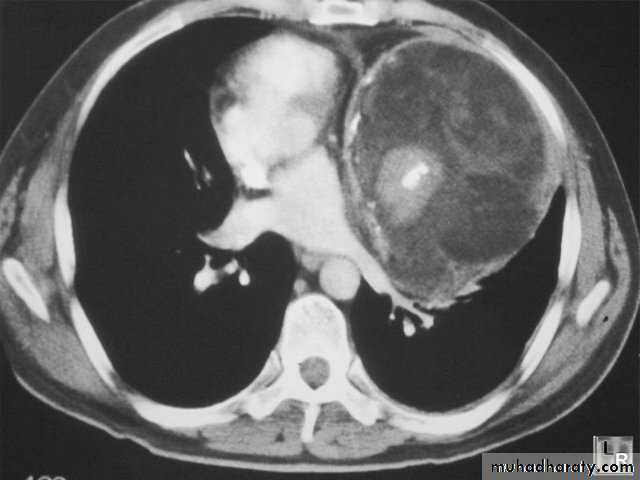

Pulmonary hydatid disease

Hydatid cystX-ray findings

Simple hydatid cyst

Signet ring

Double arch sign

Water lily sign

A/F level